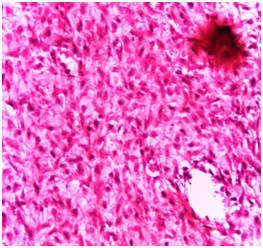

Histologically, the overlying epithelium displayed signs of pseudoepitheliomatous hyperplasia. The connective tissue revealed an impressive myxomatous background, in which lobules of myxoid areas were conspicuous (Figure 2). Evident in the histological field was the occasional peripheral bone formation, which embraced the myxomatous stroma (Figure 3). The focally rich fibrocellualrity of the lesion should neither mitotic figures nor cellular atypia. Neither granuloma formation nor malignant features could be appreciated (Figure 4). The diagnosis was, accordingly, an ossifying fibromyxoid tumor. Regarding confirming the diagnosis of OFMT, no immunohistochemical markers were indicated because no specific markers are adjunctively recruited in the medical literature. A follow-up interval was determined: every 6 months. The patient was educated about the necessity of compliance.

Figure 4 Photomicrograph showing a focally rich fibrocellualrity of the lesion with neither mitotic Figure nor cellular atypia. (H&E stained, Original magnification: 40x).